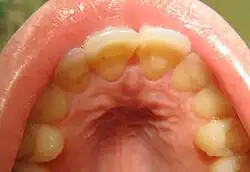

Loss of enamel (acid erosion) from the inside of the upper front teeth as a result of bulimia

People with bulimia are at a higher risk to have an affective disorder, such as depression or general anxiety disorder. One study found 70% had depression at some time in their lives (as opposed to 26% for adult females in the general population), rising to 88% for all affective disorders combined.[24] Another study in the Journal of Affective Disorders found that of the population of patients that were diagnosed with an eating disorder according to the DSM-V guidelines about 27% also suffered from bipolar disorder. Within this article, the majority of the patients were diagnosed with bulimia nervosa, the second most common condition reported was binge-eating disorder.[25] Some individuals with anorexia nervosa exhibit episodes of bulimic tendencies through purging (either through self-induced vomiting or laxatives) as a way to quickly remove food in their system.[26] There may be an increased risk for diabetes mellitus type 2.[27] Bulimia also has negative effects on a person's teeth due to the acid passed through the mouth from frequent vomiting causing acid erosion, mainly on the posterior dental surface.